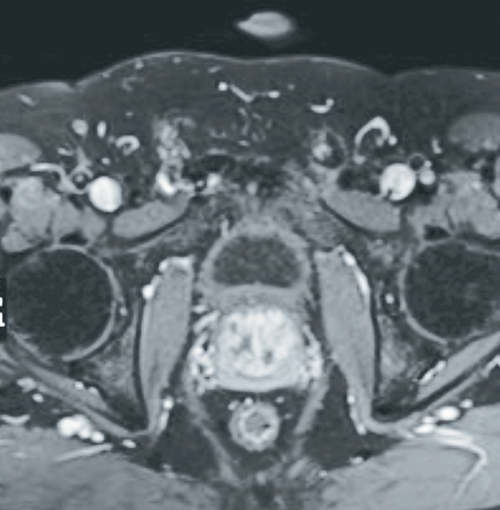

Most procedures take approximately two to three hours to complete and are well tolerated. All patients are prescribed Ciprofloxacin 750mg BD for five days along with non-steroidal anti-inflammatory drugs (NSAIDs). A follow-up contrast-enhanced MRI study of the prostate three months post-procedure is arranged to assess the degree of hypoenhancement and shrinkage of the prostate gland (Figure 2).

Figure 2: Axial T1 weighted fat-saturated post-gadolinium contrast image of the pelvis demonstrating patchy foci of hypoenhancement consistent with devascularisation seen post-prostate artery embolisation.